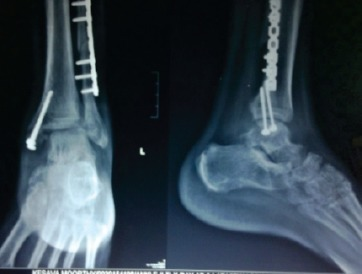

AP and lateral radiographs of the ankle demonstrating a Weber B bimalleolar ankle fracture. The fibular fracture is at the level of the syndesmosis (trans-syndesmotic). There is an associated transverse medial malleolar fracture. The mortise view shows lateral talar shift with increased medial clear space (>4mm) indicating deltoid ligament injury or medial malleolar fracture. The posterior malleolus is intact on lateral view.